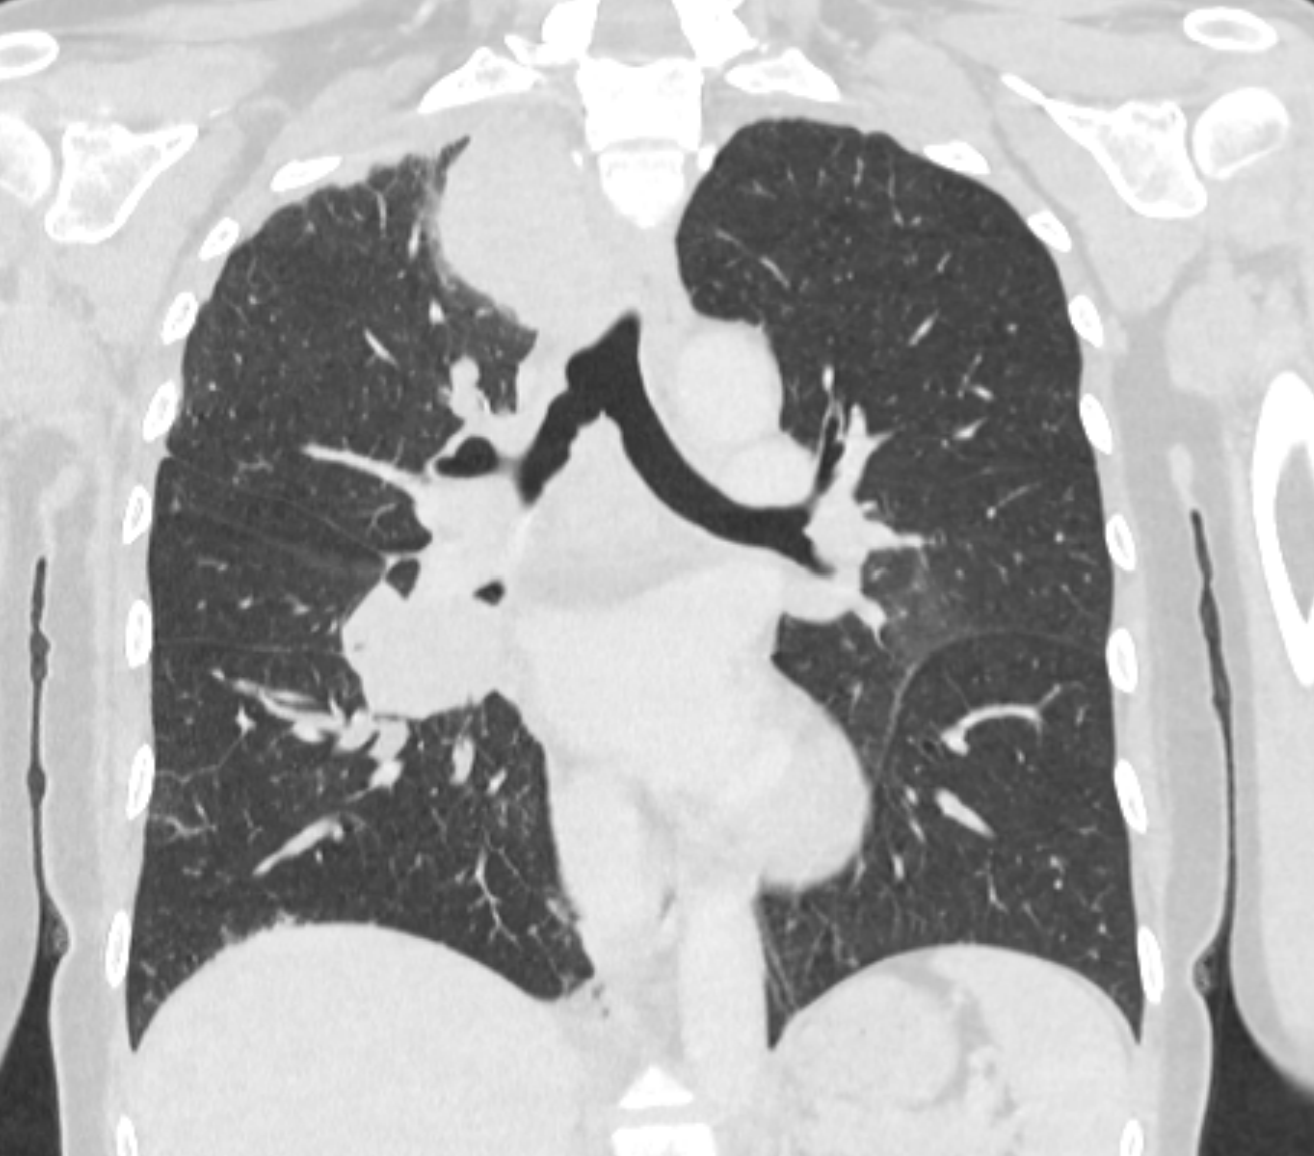

TC_5ano

Tomografia computadorizada de tórax. Observam-se linfonodos peribrônquicos aumentados, alguns com sinais de invasão brônquica, associados a múltiplos nódulos pulmonares bilaterais, sendo o maior localizado no lobo superior do pulmão direito. Achados sugestivos de disseminação metastática no contexto de câncer de mama.